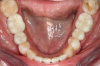

Fig 22. 12 weeks postoperatively.

Figure 22